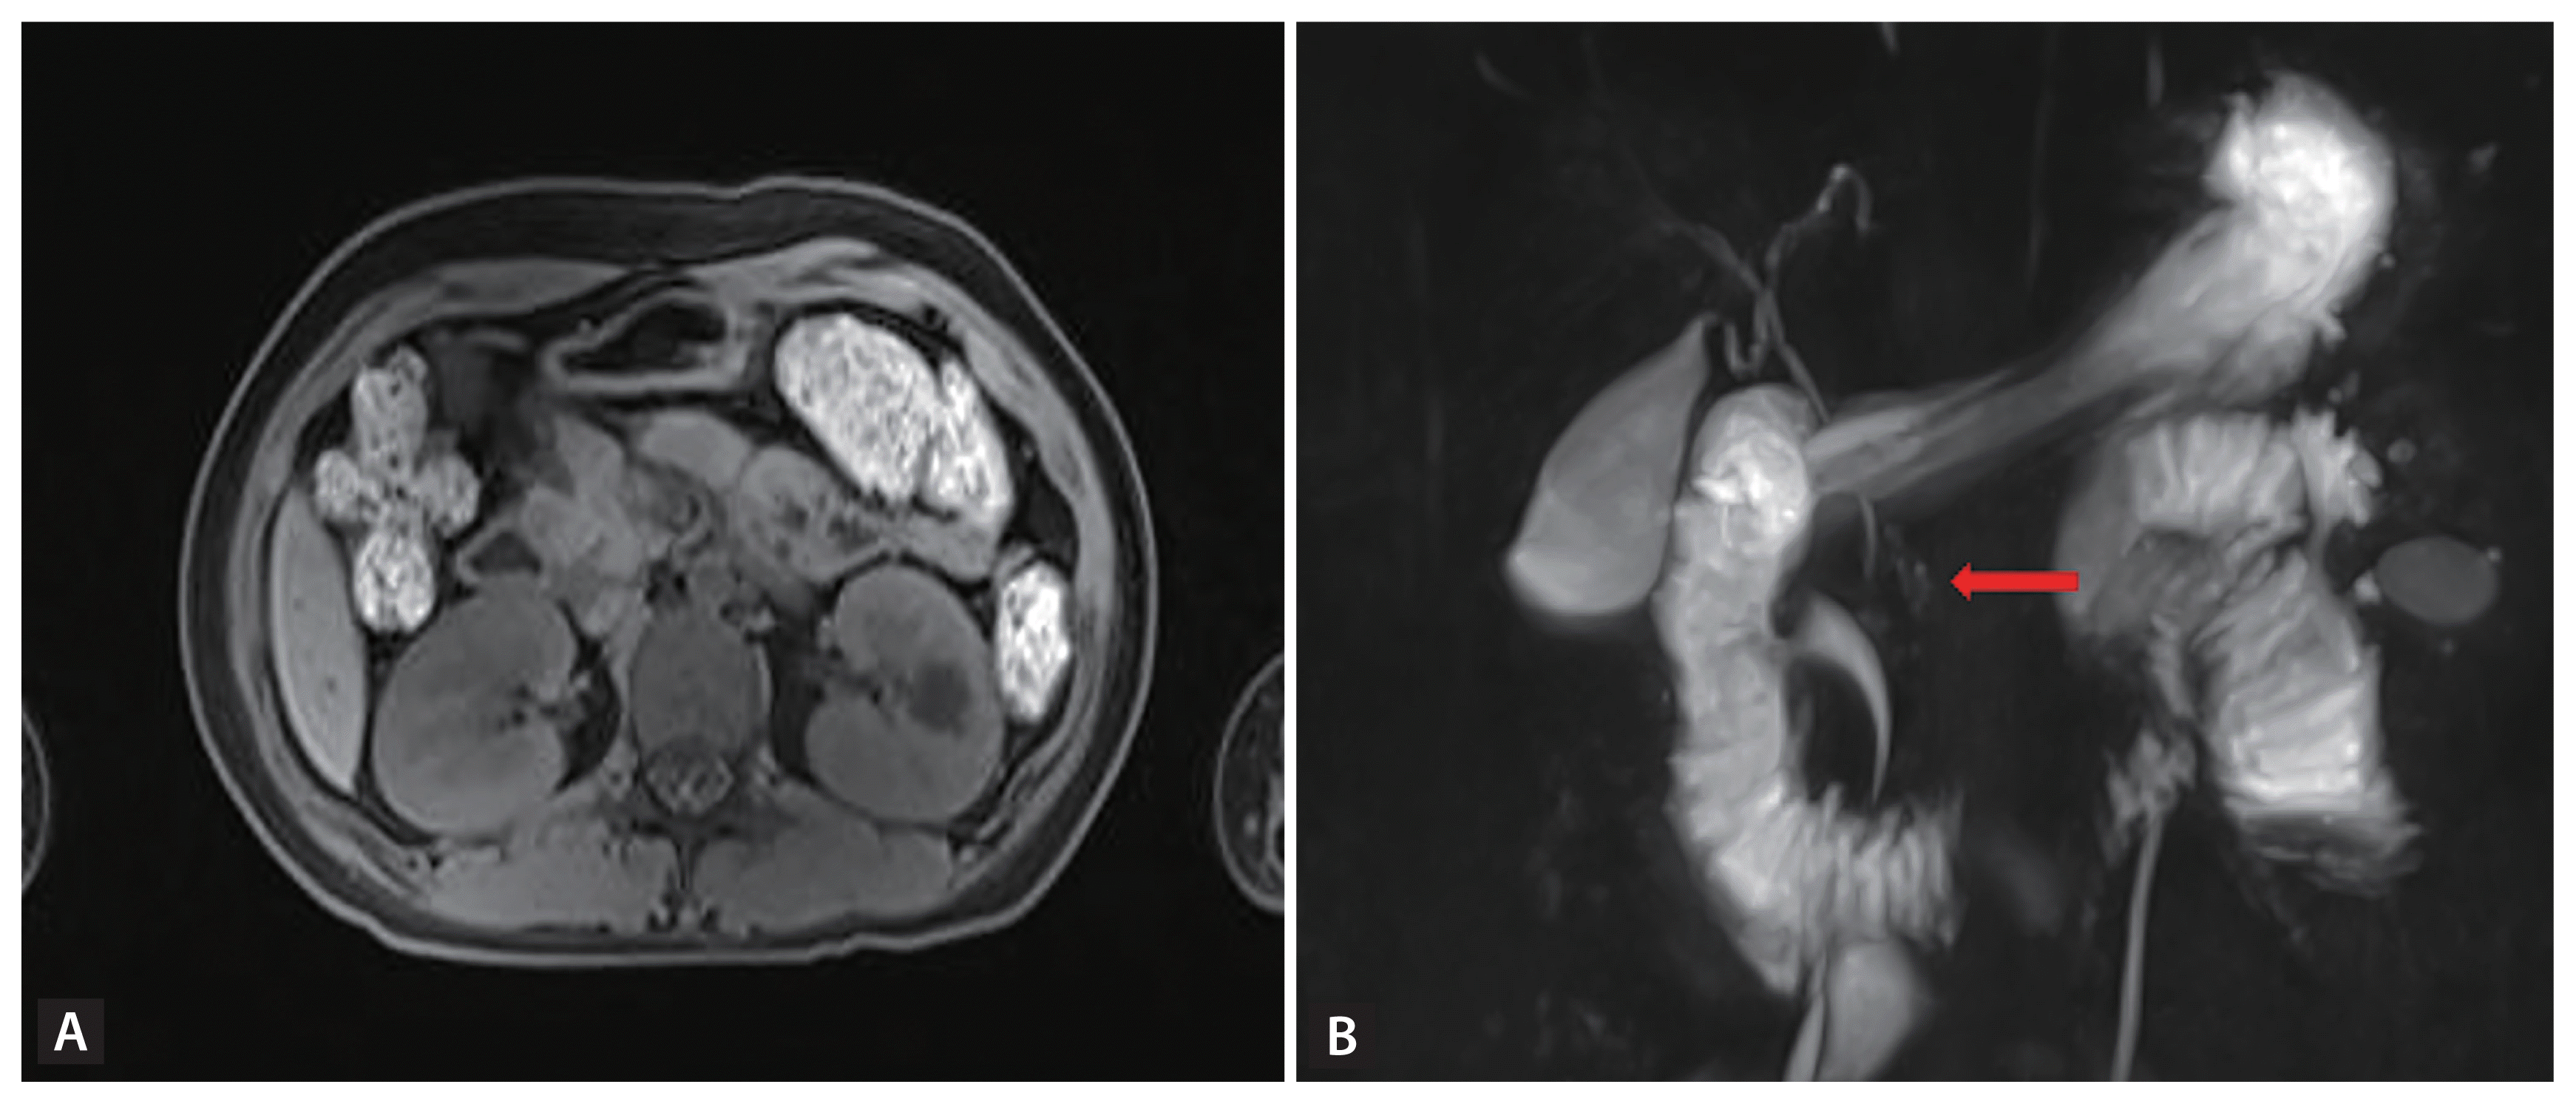

A 14-year-old girl without any previous disease presented to us with abdominal pain and vomiting. Her blood pressure and body temperature were 125/81 mmHg and 37.1°C, respectively. The laboratory findings were as follows: white blood cell count 27,530 × 109/L, hemoglobin 11.7 g/dL, platelet count 408 × 109/L, arterial blood gas analysis (pH 6.906, HCO3 1.7 mEq/L, anion gap 37.3), serum glucose 421 mg/dL, hemoglobin A1c 9.7%, total cholesterol 500 mg/dL, triglyceride 2,051 mg/dL, high-density lipoprotein cholesterol 16 mg/dL, low-density lipoprotein cholesterol 59 mg/dL, amylase 979 U/L, lipase 987.5 IU/L, serum ketone 1.4 mmol/L, serum insulin 9.85 μIU/mL, and C-peptide 0.83 ng/mL. She was diagnosed with diabetic ketoacidosis (DKA) accompanied by acute pancreatitis, and received intensive treatment including hydration, insulin administration, and fasting. Enhanced abdominal computed tomography performed on hospitalization day 14 revealed the absence of pancreatic tissue in the body and tail of the pancreas (Fig. 1). Magnetic resonance cholangiopancreatography was also performed (Fig. 2). Agenesis of the dorsal pancreas (ADP) is an extremely rare congenital anomaly characterized by the absence of the pancreatic neck, body, and tail. Most cases are asymptomatic, and the diagnosis is usually incidental during evaluation for an unrelated issue. Abdominal pain, pancreatitis, weight loss, diabetes, and jaundice are the most commonly associated symptoms and diseases. According to published reports, approximately 50% of patients with ADP also have concomitant hyperglycemia. DKA and severe hypertriglyceridemia complicated by pancreatitis in a patient with ADP has rarely been reported, while ADP initially presenting with DKA accompanied by pancreatitis in early adolescence has never been described earlier.

Figure 1

Contrast abdominal computed tomography scan shows the pancreatic head (A, red arrow), while the pancreatic body and tail are absent (B, red arrow). The head of the pancreas is diffusely enlarged with perilesional fat infiltration.